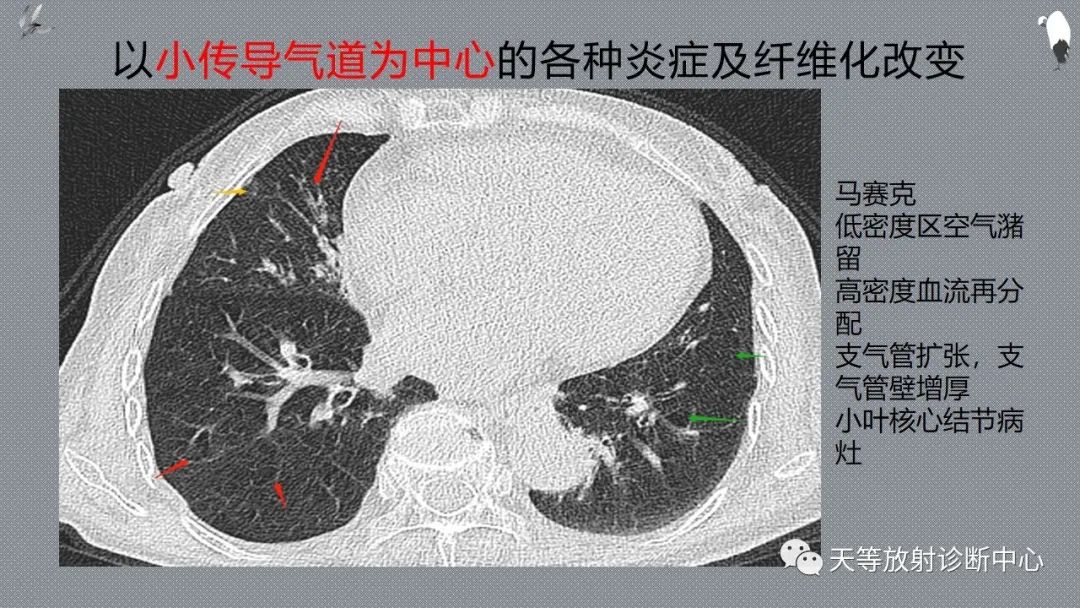

细支气管是以小传导气道为中心的各种炎症及纤维化改变

包括缩窄性细支气管炎及闭塞性细支气管炎伴机化性肺炎(BOOP)